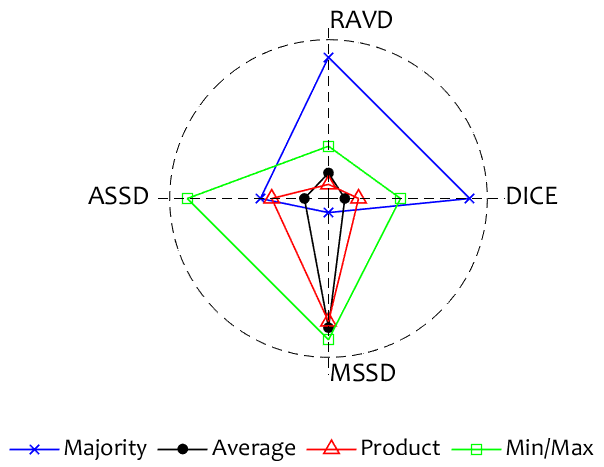

Finally, to be able to recommend one of the ensemble models, we present two glyph plots in Figures 4 and 4. The plots are based on the averaged testing results for each metric. DICE was reversed so that small values are more desirable. The ensemble scores for each metric were scaled between 0.1 and 1 and plotted on the spokes of the glyph plot. An ideal ensemble would occupy a small square in the middle. The larger the surface of the figure presented by the ensemble, the worse the ensemble in comparison with the rest. The Chaos dataset figure elects the Majority Vote ensemble as the best, closely followed by the Average ensemble. On the other hand, the Majority Vote ensemble occupies a large area in the glyph plot in Fig. 4. The Average ensemble is the best for this data set.